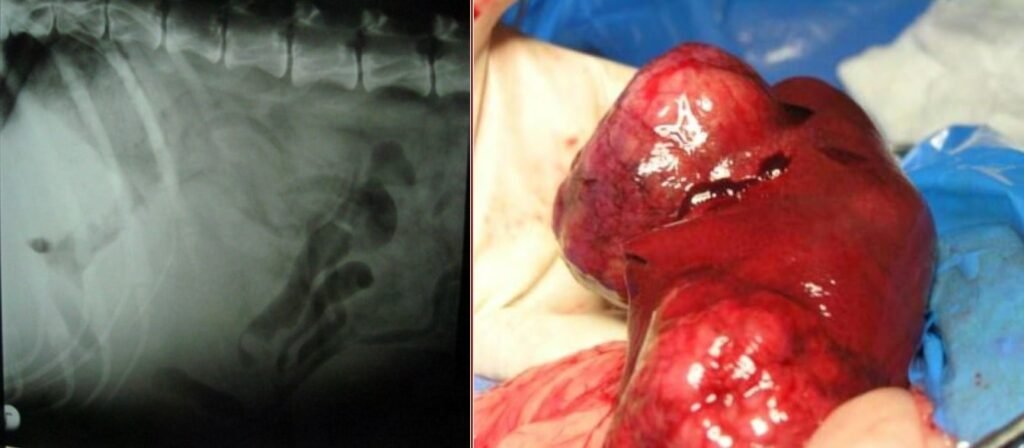

Common surgical affection of stomach and cardia in dogs is Gastric dilatation and Volvulus (GDV) that need immediate surgical intervention.